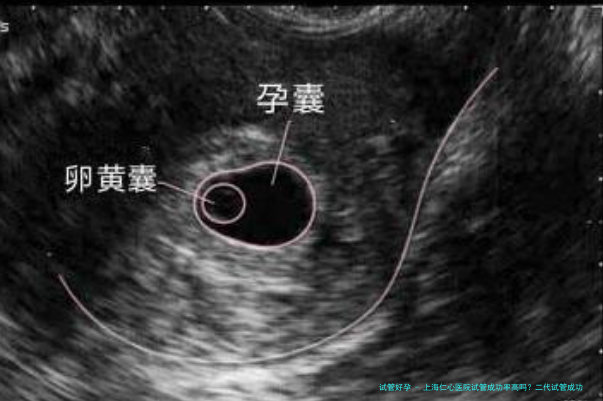

2026年上海仁心医院第2代试管婴儿的成功率平常在50%~55%左右,年轻病患的成功率可以更高。确实是中国辅助生殖业界全体实力较强的医院。上海仁心医院在上海十大试管婴儿医院中排行第一,在中国十大试管婴儿医院中排名第一。因此在医院生殖医院制作第2代试管是非常靠得住的,但实质成功率取决于患者的健康状况和精子和卵子的质量。

上海仁心医院生殖医院创造于2001年。目古人工授精技术、人工授精技术、基本试管受孕-胚胎移植、卵子内单精子显微注射技术、植入前胚胎遗传诊断技术已经进行了五项技术。辅助生殖不同技术的成功率下述: